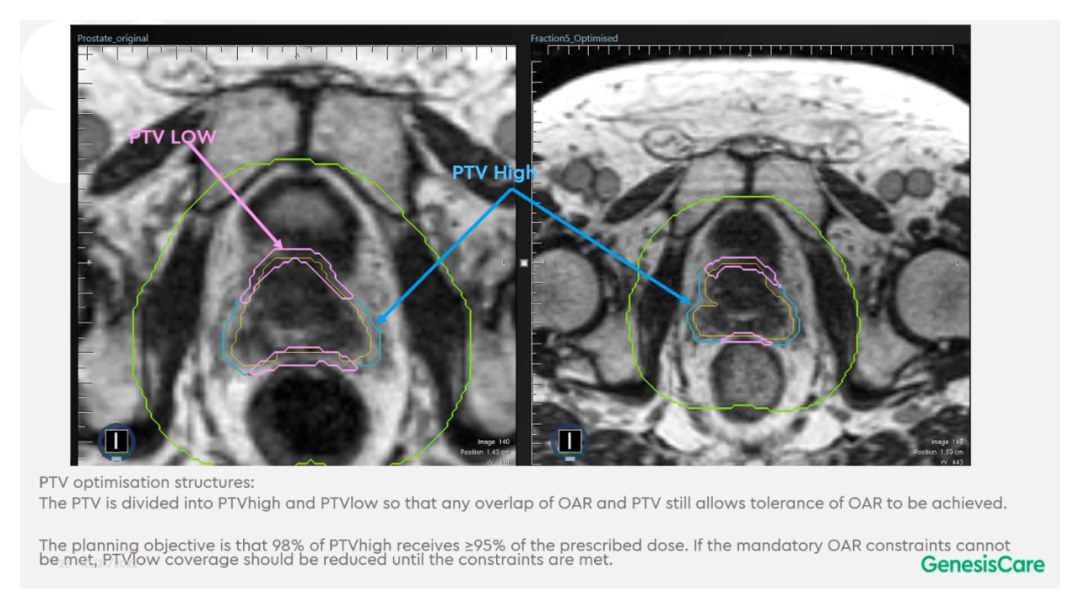

Dr. Camilleri表示,他们在做在线自适应放疗的时候,为了提高速度,仅对靶区外放3cm以内的危及器官的变化进行自适应调整或重新勾画轮廓,见Figure 13。这样可以缩短轮廓勾画的时间。对于放疗计划,使得95%的靶区体积接受到100%的处方剂量覆盖,并将最大剂量限制为2%的靶区体积不超过处方剂量的110%,这样就能保证在图像上很难显示的尿道不会超量,见Figure 14。另外,在制作放疗计划时,将PTV分为PTV LOW和PTV High,PTV和危及器官重叠的部分为PTV LOW,将PTV LOW的剂量目标设定在危及器官的耐受剂量以下,这样就能保证危及器官不超量,见Figure 15。